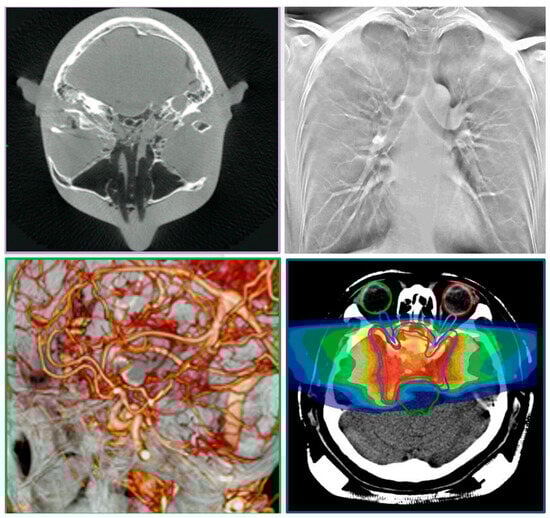

| 2D radiography (see Figure 5, Figure 6, Figure 11 and Figure 16) | See detector a, b, c resolution | 1 s to 2 min/1–360 | ~50/50/50 | SID 50–1100/ everything else is variable |

| 3D CT (Figure 2 and Figure 12) | 80–200 μm full CT, 3x mode CT, half-beam mode, stacked-volume mode | 6 s to 4 min/40–5000 | ~50–500/16.4–200/62–120 Total dose in full in vivo high-res. CT: 6.2 mSv | 700/480/240/0.06 |

| 3D tomosynthesis (see Figure 2 and Figure 11). Optical mag., x4 | 10–40 μm fixed detector, moving emitter | 6 s to 2 min/5–5000 | ~30/16.4/34 | 50–1100/variable SOD/variable VD and VH/0.02–0.2 |

| 3D dynamic imaging stereovideography (Figure 5, Figure 6 and Figure 9) | 20–200 μm Static or moving image intensifiers with high-speed cameras | 1 s, as required by IR/10–10000 | 0.02–1.1 mSv min−1/0.08–0.9 mSv min−1/0.02–0.08 mSv min−1 | 50–1100 /10–500/variable VD and VH/0.02–0.2 |

| 3D “microCT” optical and geometrical magnification x4 (Figure 2 and Figure 13) | 0.02 mm Emitter/detector rotation only | 1 min to 5 min or as required/100–5000 | 0.2–5 mSv min−1/not available/0.2–5 mSv min−1 | 50–100 /10–50/variable VD and VH/0.02 |